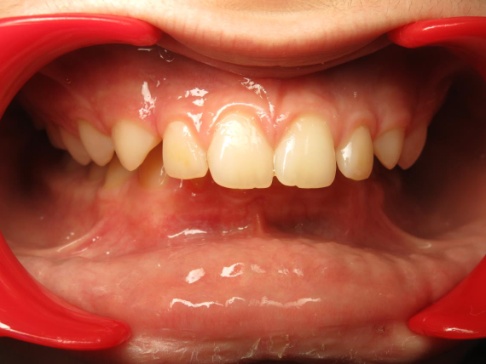

1 - Arcades dentaires avant-après

Les arcades dentaires montrent un décalage majeur de classe II, avec des incisives inférieures en position très reculée, venant directement au contact du palais. Cette configuration traduisait un déséquilibre squelettique important entre maxillaire et mandibule. Le traitement a consisté en une préparation orthodontique rigoureuse, suivie d’une chirurgie orthognathique permettant de repositionner les bases osseuses et de restaurer une occlusion fonctionnelle.